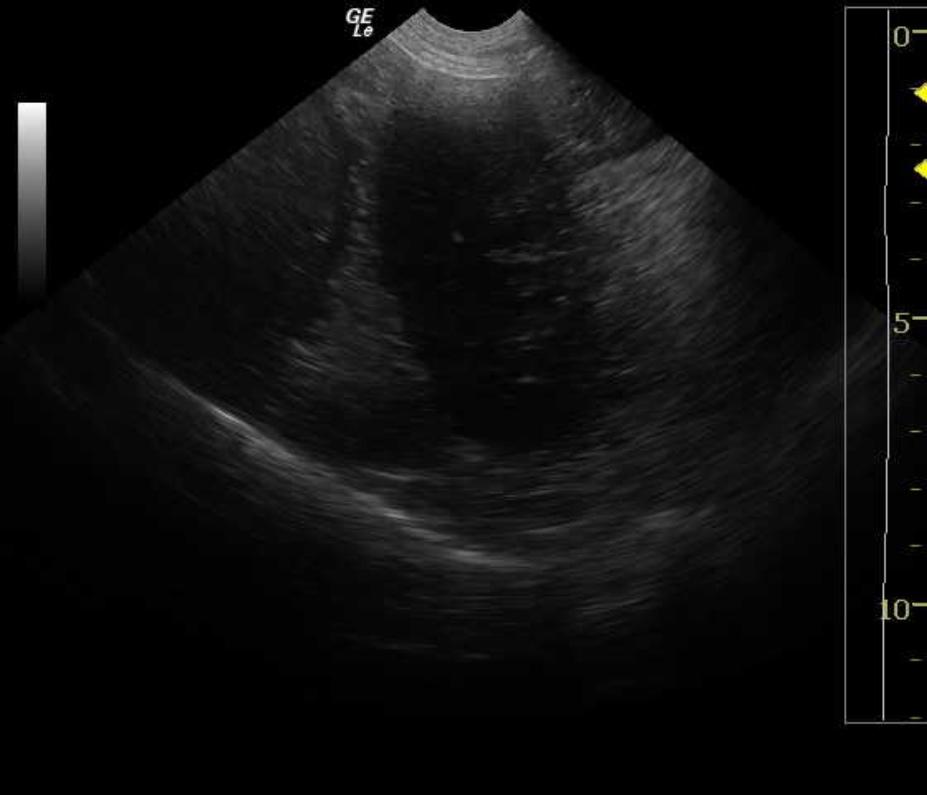

5 year old FS Labrador retriever was presented for repetitive vomiting, hematemesis, severe halitosis, lethargy and depression. Lateral and ventral/dorsal radiographs revealed a dilated stomach to four times its normal size, as well as dilated loops of bowel dorsal to the stomach. Hypokalemia and hypochloremia were present on the serum biochemical profile. Leukocytosis was present on the CBC and the SNAP 4DX® test was negative.